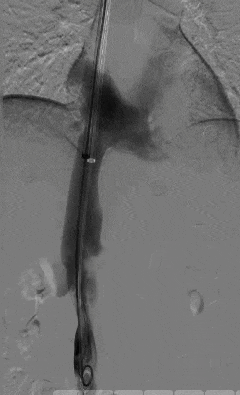

血栓拦截网

下腔静脉滤器 是临床预防下肢深静脉血栓或肺动脉栓塞的常用介入装置,通常被放置在肾静脉下方的下腔静脉内,如同血管内的「血栓拦截网」,

它能有效阻挡脱落的大块血栓随血液流动引发致命的肺动脉栓塞,为血栓患者的治疗保驾护航。

但需注意,滤器属于体内异物,并非永久性植入装置,长期留置可能引发多种并发症,因此滤器取出术成为必要的后续操作。